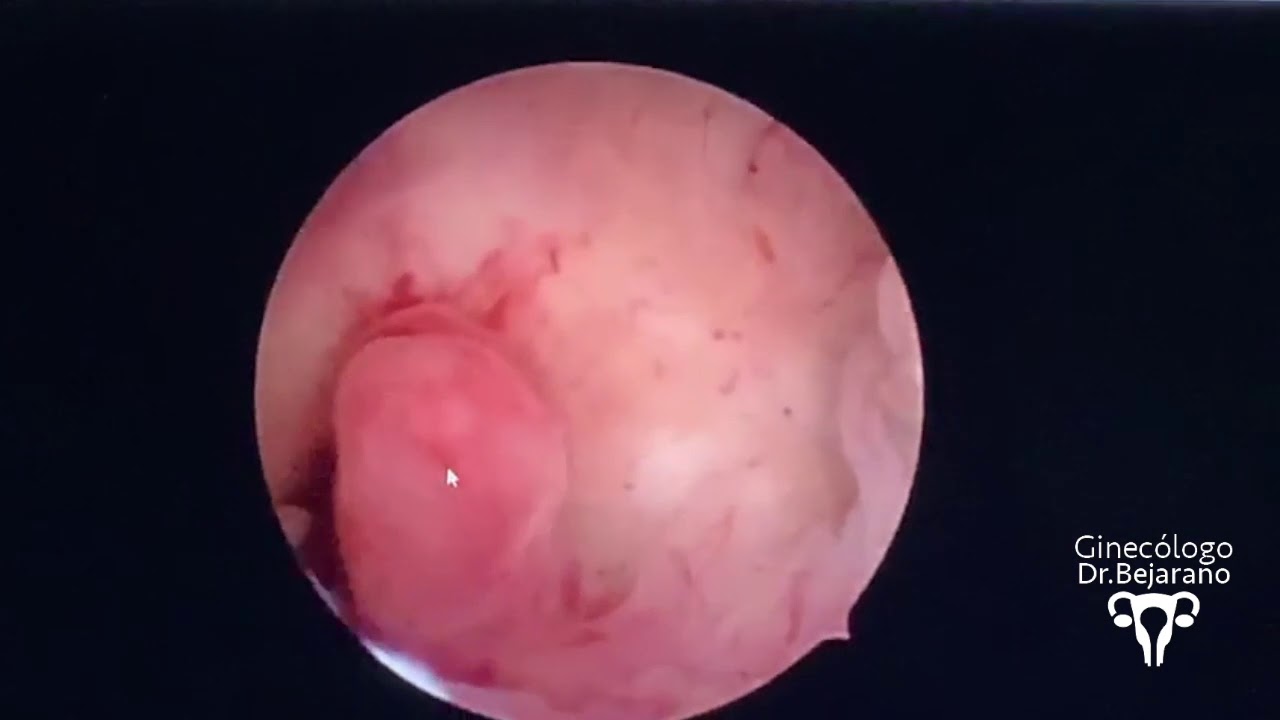

HISTEROSCOPIA diagnóstica || PODEMOS tener un BEBÉ || Pulpito's Family #histeroscopia

Source: Youtube.com